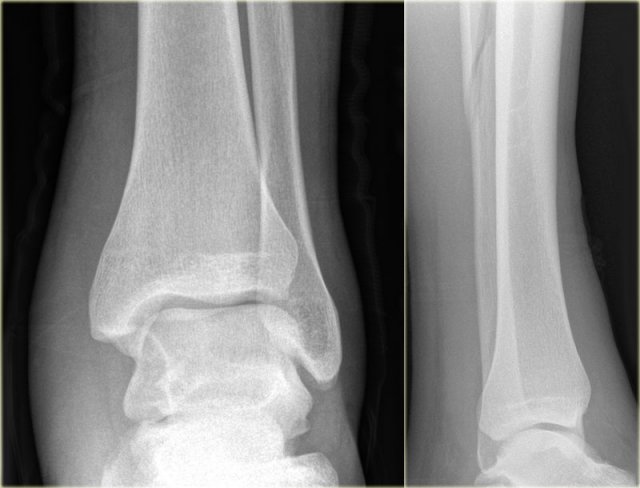

Example 4

• Basic interpretation

Fracture of the lateral malleolus starting anteriorly at the level of the joint extending proximally posteriorly.

• Classification

The fracture is classified according to Weber as a type B fracture.

According to Lauge Hansen the oblique fibular fracture indicates that this is a Supination Exorotation injury stage 2 or higher.

• Re-examination

Look for stage 3 and stage 4.

There are subtle findings which indicate a fracture of the posterior malleolus. Normally you probably would not have noticed these.

On the lateral view the posterior cortex of the tibia is interrupted indicating a fracture (blue arrow).

Even on the AP-view there are subtle findings that indicate a fracture (red arrows).

There is a widened medial clear space, which indicates a rupture of the medial collateral band, i.e. stage 4.

• Final report

Weber B fracture. According to Lauge-Hansen this is a SER stage 4.

This is an unstable fracture with dislocation that needs surgical repair.